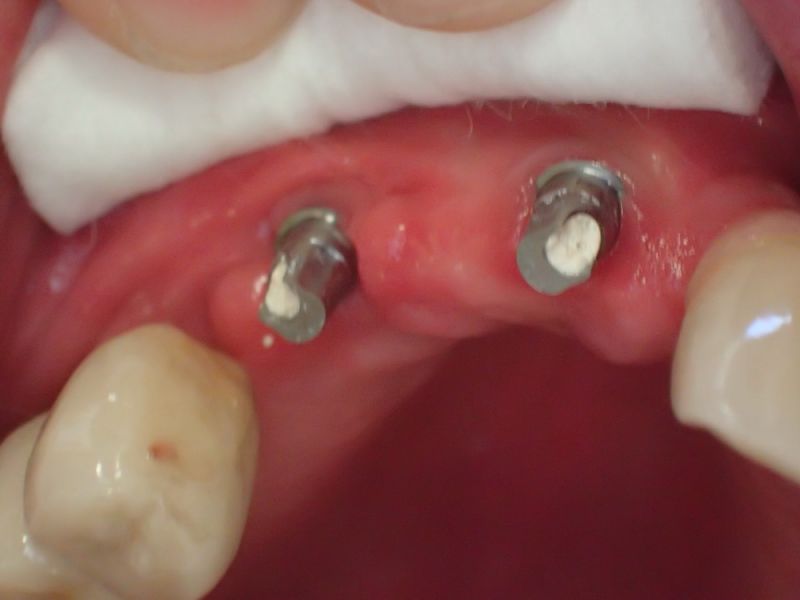

Kieler Patient erhält implantatgetragene Frontzahnbrücke

Dieser Patient fällt ein bißchen aus dem üblichen Rahmen, weil die vielfachen Versorgungen hier nicht zeigtlich im Rahmen einer CMD Behandlung erbracht wurden, sondern über viele Jahre hinweg nach und nach.

Was man an diesem Fall gut zu erkennen vermag, dass Patienten, die für sich irgendwann entschieden haben, nicht mit einem herausnehmbaren Zahnersatz ihren Lebensabend verbringen wollen auch nach und nach auf eine Implantatpfeilerstützzahl kommen, die genügend Substanz für die Lebensphase bieten, in der körpereigene Stützsubstanz, in Form von Zähnen zunehmend verloren geht.